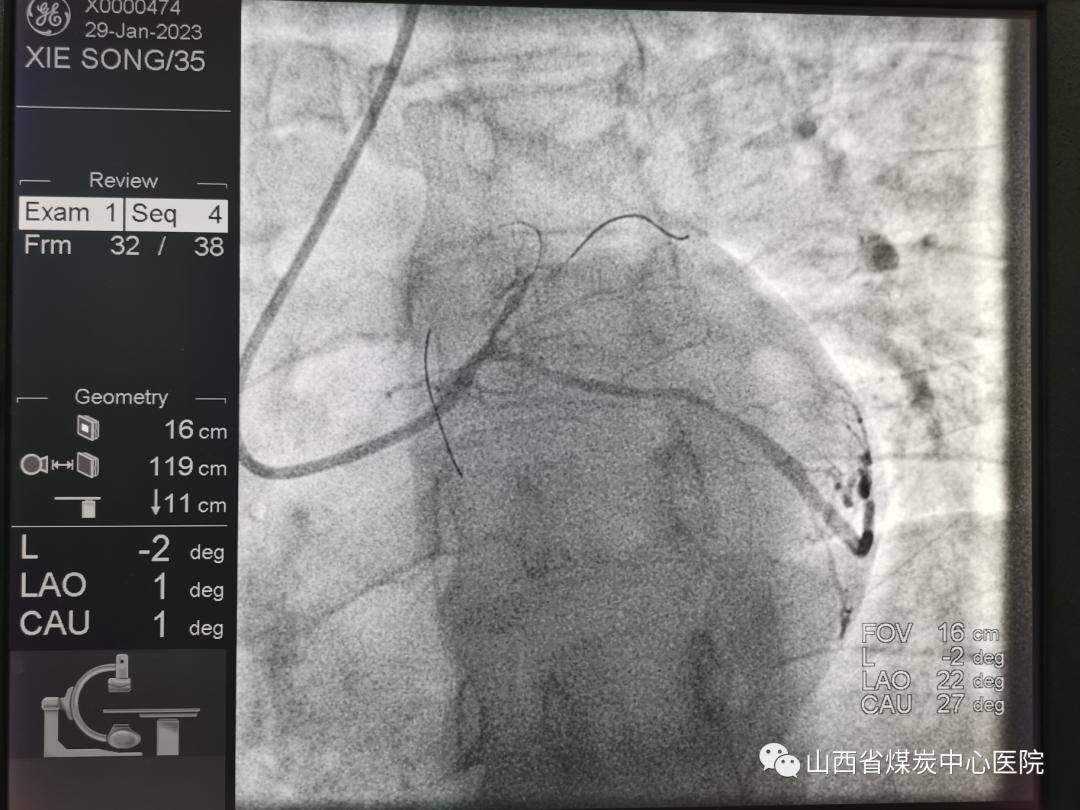

冠状动脉造影显示前降支急性闭塞,立即开通!导丝顺利通过,球囊扩张。冠脉血流恢复了,患者症状缓解了,但是血管有狭窄,狭窄处“发白”。一个刻不容缓的问题出现了“35岁这么年轻,要放支架吗?”手术台前的暴清波主任没有犹豫,立即启动腔内影像学检查。

冠脉光学断层扫描(OCT)提示前降支近中段病变处斑块侵蚀无破裂,狭窄70%左右。可以继续药物控制,不放支架、精准治疗、介入无植入。